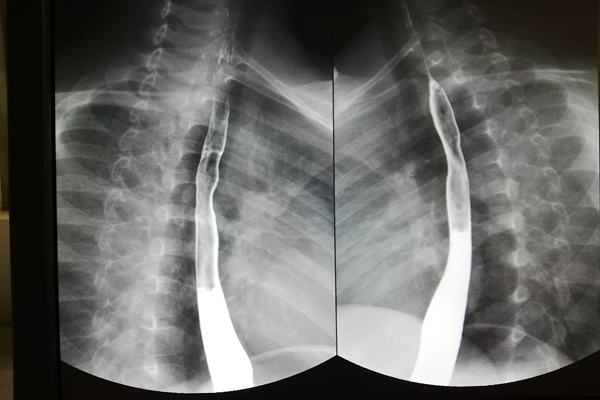

该患儿因误食烧碱后出现吞咽困难出现口腔、胸骨后疼痛,口腔充血糜烂,当地医院给予洗胃等处理,伤后3天食管镜检如常,其后开始进食,发现进食顺利;伤后半月起逐渐出现吞咽不畅,逐渐加重偶伴呕吐,诊断为食管狭窄。曾就诊于西安多家大型医院均因诊治难度大未给予明确诊治意见。之后慕名赴交大二附院消化内科董蕾教授处就诊,行内镜下食管球囊扩张治疗多次后反复出现吞咽困难,仅可进全流食。为指定详尽全面的诊治计划,联系并经小儿外科高亚教授同意后于2015年7月收住交大二附院小儿外科。入院后食管造影提示“食管主动脉弓处狭窄,仅残留直径为数毫米的孔洞”;CT及MRI检查提示“食管狭窄部位与主动脉弓分界不清”,初步诊断为食管化学性烧伤后瘢痕狭窄。科室讨论过程中,高亚教授指出该患儿具有手术治疗指征,但常规手术(食管狭窄段纵切横缝、狭窄段切除食管吻合术以及代食管手术)存在种种不足如食管狭窄段纵切横缝术为瘢痕愈合,术后可能发生吻合口漏,食管再狭窄可能性高、且难以扩张治疗,需行狭窄段切除吻合术或代食管手术;本例狭窄段位于食管中段,邻近主动脉弓和左主支气管,因碱性化学性烧伤可能引起食管全层损伤,导致食管与周围组织紧密粘连,贸然施行狭窄段切除食管吻合术手术操作有一定难度,狭窄段切除后如食管近、远端距离长,则无法吻合,或者因吻合口有张力,术后出现吻合口漏及食管再狭窄风险加大。除上述常规手术外,高亚教授复习文献,结合患儿实际病情指出采用食管磁压榨吻合术即内镜下将一块磁铁经口腔置入狭窄段上方食管内,将另一块磁铁经胃造口通过贲门置入狭窄段下方食管内,两块磁铁相互吸引,狭窄部可因磁铁的压迫缺血而致坏死脱落,食管壁增生愈合,从而恢复食管的连续性。完成吻合后磁铁可经肠道自行排出体外或通过内镜取出。此方法相当于食管缓慢扩张 + 食管延长 + 狭窄段切除食管吻合术,具有操作简便、微创的优点。术后亦存在再狭窄可能,但由于原狭窄段已经切除,新吻合口狭窄易于内镜扩张治疗。此外,我校吕毅教授团队有较成熟的成人磁压榨治疗经验,可提供相关技术支持。

告知并取得患儿家长同意并经过充分的术前准备、多次院内(校内、国内)多学科会诊、院内伦理审查、专门加工吻合器具后,在吕毅教授、董蕾教授团队的协助支持下,高亚教授团队于2015年11月26日率先在国内施行首例磁压榨吻合术治疗小儿食管狭窄,术中操作顺利,时间约60分钟,无手术并发症;术后2周内复查胸片提示磁环未发现磁环异位、扭转、成角、滑脱,且磁环间距逐渐缩小至不足1mm,胃镜检观察食管内磁环对合良好;术后第18天在内镜下借助抓钳的牵拉,磁环顺利脱落进入胃腔并在经导丝牵引下顺利自胃造瘘口处取出,胃镜下探查食管吻合处通畅,无明显狭窄,粘膜光滑无瘢痕形成,无明显渗、出血及食管破裂等。术后复诊间隔1月,来院随访至今共12月,术后间隔1月行食管扩张术、放置支架2次预防再狭窄,胃镜复查未见异常,患儿进食正常,经评估患儿身高、体重均在同龄儿平均水平之上。